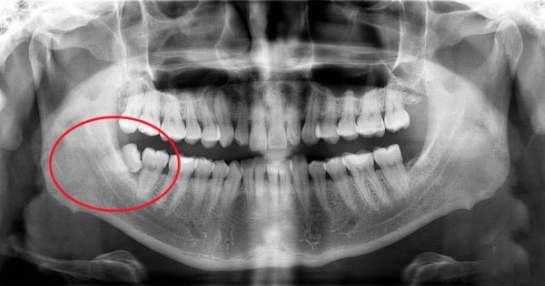

想要了解自己的智齿长什么样子,

可以到家庭医生口腔免费拍全景片,

智齿生长情况一目了然~

口腔全景片